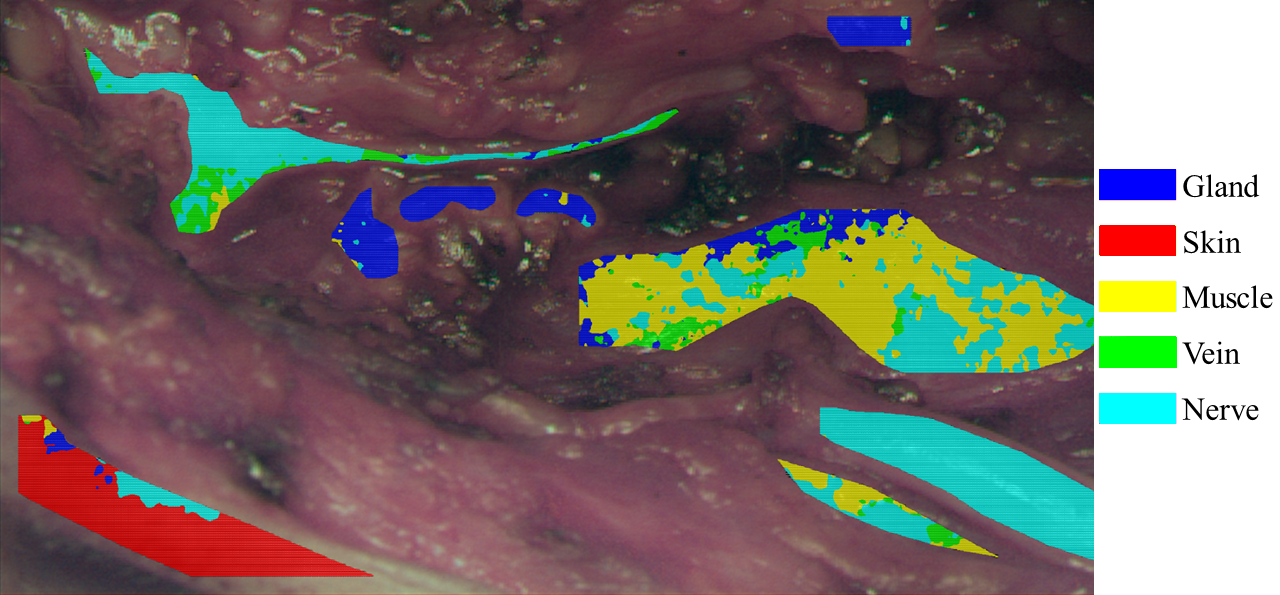

Fig. 2: The different tissue regions, annotated by the surgeon, are bordered using specific color coding.

The annotations of the individual tissue types were carried out by the performing surgeon directly after image acquisition, resulting in specific well defined tissue areas. Figure 2 exemplary shows the annotation regions of Figure 1. The annotated tissue areas are divided into patches of 31×3131\times 31 pixels in spatial dimension by a sliding window approach with stride of 1010 for training the network. Care is taken to ensure that only one type of tissue is included per patch. In total, more than 80.00080.000 patches has been created; however, the distribution of the patches across the individual tissue types is highly inhomogeneous, with more than 43%43\% of the patches being muscle, cf. Figure 3.

If the trained network is not applied to individual patches but to complete hyperspectral images, a visualization of the tissue classification can be obtained by overlaying the prediction results on the calculated RGB representation. Such augmented reality (AR) visualization holds potential for intraoperative use, providing surgeons with real-time feedback on tissue classification. A sample output of the best-trained CNN is visualized in Figure 5. For analytical purposes, only previously annotated tissue areas are visualized with the network's prediction. Across all classes, the visualization demonstrates good recognition performance, mirroring the same overall accuracy as the patch-wise analysis. Notably, muscle exhibits the poorest prediction, consistent with the findings of the patch-wise analysis as depicted in Figure 4. Unfortunately, veins are not visible in this example, i.e., they have not been annotated. Nevertheless, individual pixels in other tissue areas have been classified as veins.

Fig. 5: Predicted areas in an evaluation image, cf. Fig. 2.